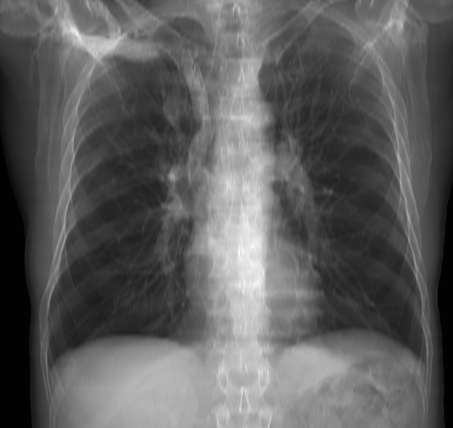

In Figure 5 we display example results on a real chest X-ray image. An enhancement weight factor w𝑤w is used to factor the extracted lung image. By controlling w𝑤w, multiple enhancement levels can be achieved.

Refer to caption

Figure 5: NIH Chest X-Ray-14 case #1555 Enhancement Results